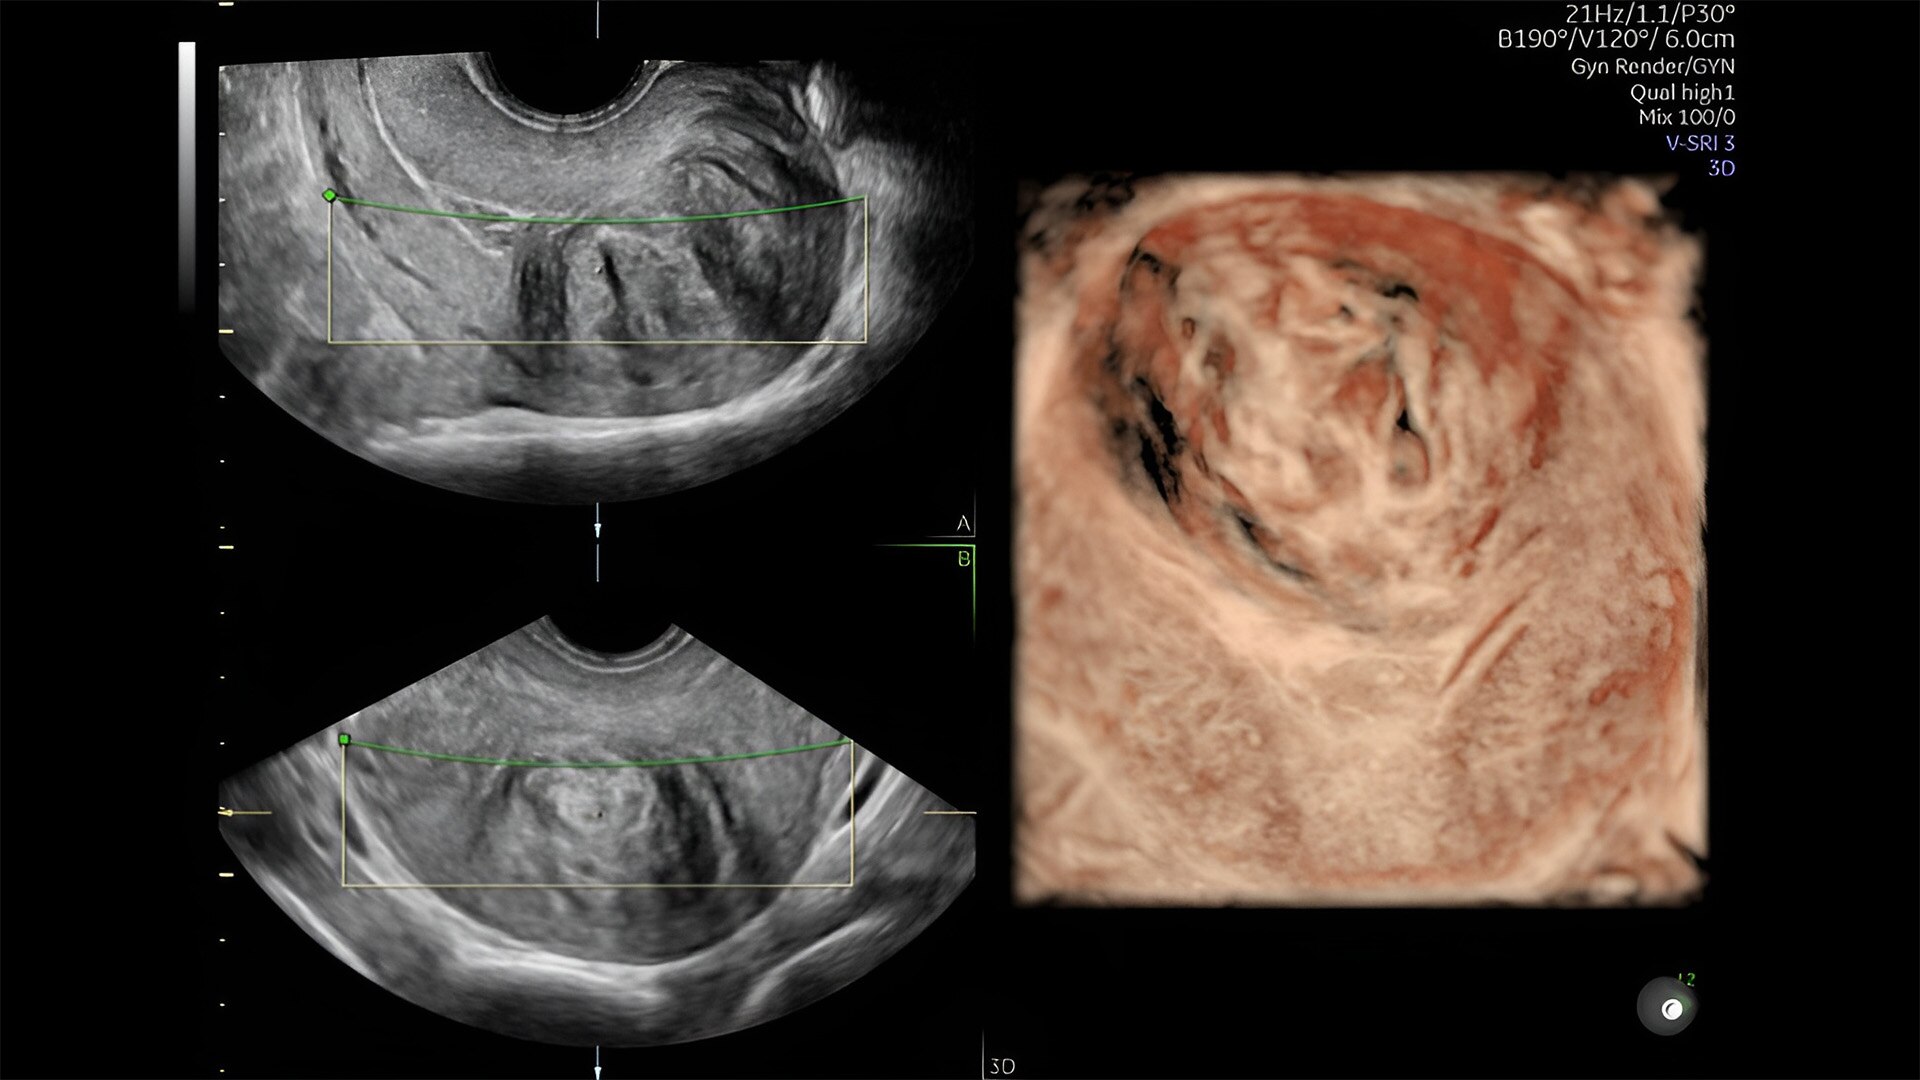

Detect the undetectable

Discover complicated anomalies and pathologies with the Voluson Expert 22 to provide answers sooner for better decision making.

Complex cases come with enough uncertainty. That's why the Voluson Expert 22 is specifically designed for in-depth assessment of complicated anatomy — with pioneering first trimester, fetal cardiac, gynecological, and other pivotal technologies that focus on early detection and intervention.

Pelvic health

Offer patient answers faster with Ai-based automation tools